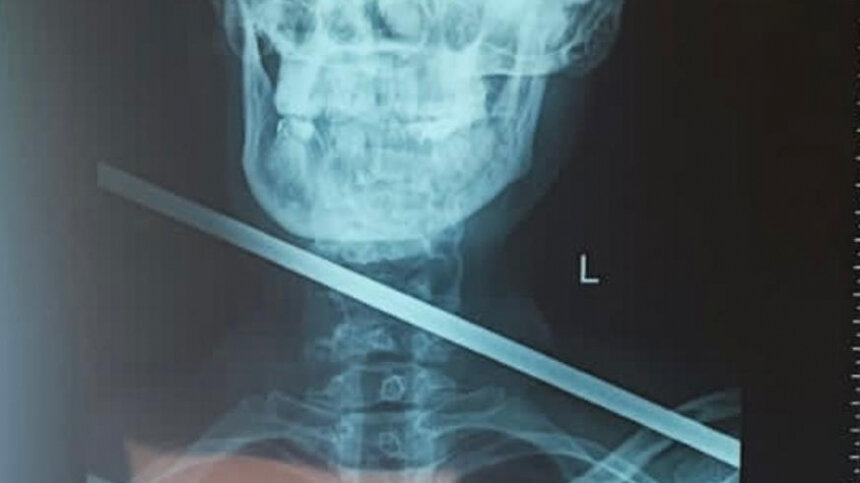

Родилась в рубашке: врачи спасли женщину, которой сосед стрелой пронзил насквозь шею

Мужчина выстрелил в нее из гарпуна. Выжила она чудом.

Недавно в Приморском крае произошел вопиющий случай. В поселке Трудовое соседи выясняли, кто у кого крал электричество. В итоге конфликт дошел до того, что один из жителей населенного пункта достал самодельный огнемет. Когда другой сосед попытался отобрать оружие, мужчина опалил его. Под руку попалась и женщина. Разъяренный приморец выстрелил в нее из гарпуна, пронзив ей насквозь шею. Выжила она чудом.

«Под общей анестезией была проведена ревизия раны, частично была повреждена щитовидная железа, после удаления инородного тела, железу удалось сохранить. По мнению врачей, такое ранение считается смертельным, в этом случае стрела не задела жизненно важные органы», — сообщает пресс-службе ведомства в своем Telegram-канале.